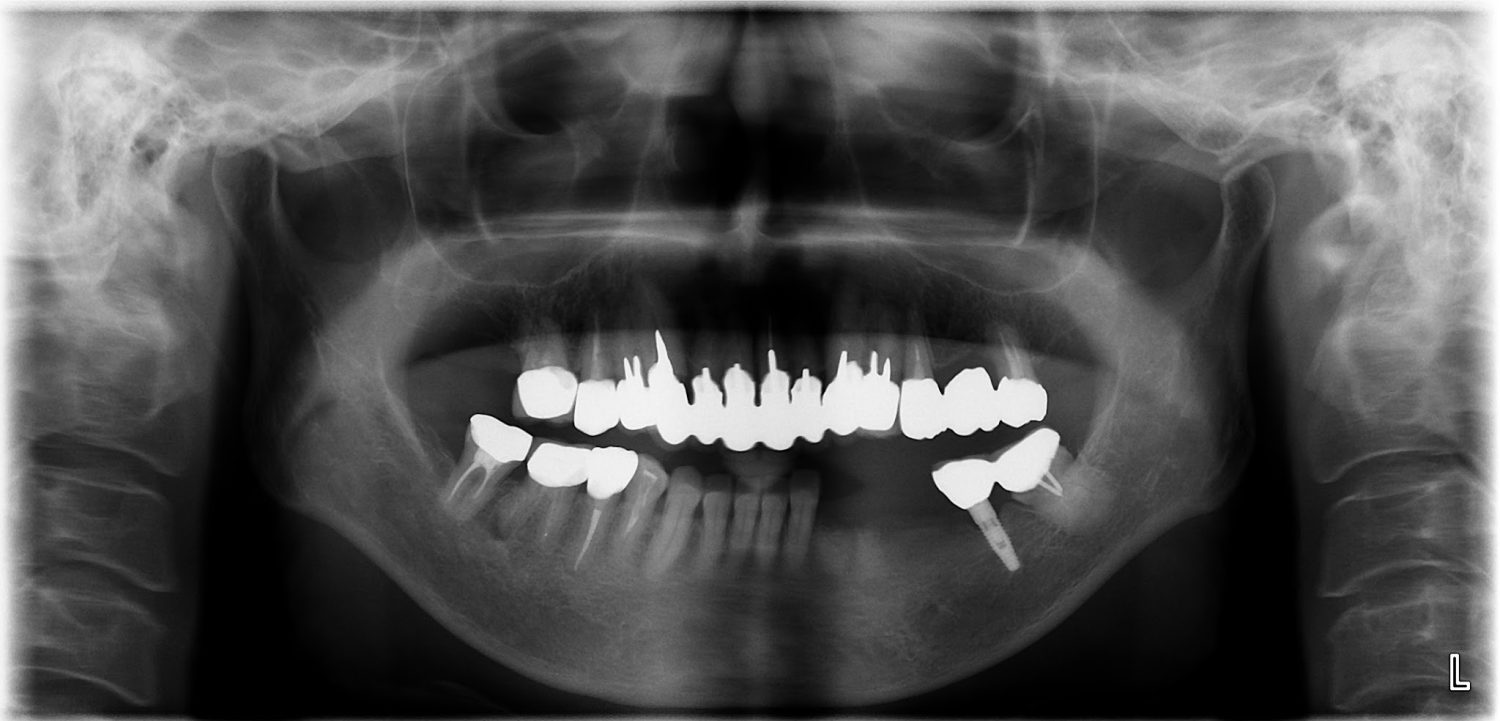

インプラント治療の症例紹介④

Before

After

主訴

義歯による疼痛

治療内容

下顎舌側に骨隆起があり義歯困難な状態。保存不可能な歯の抜歯を行い、インプラントを埋入し咬合再構成を行った。

治療費

2,851,200円(税込)

治療期間

29ヶ月

通院回数

26回

想定されたリスク

※咬合力の強い方なので、予防的にマウスピースの装着が必要。インプラント周囲炎の恐れがありました。

濱 仁隆先生

浜歯科

歯の欠損の対合歯の挺出等を修正し咬合平面を揃え咬合再構成を行った症例。